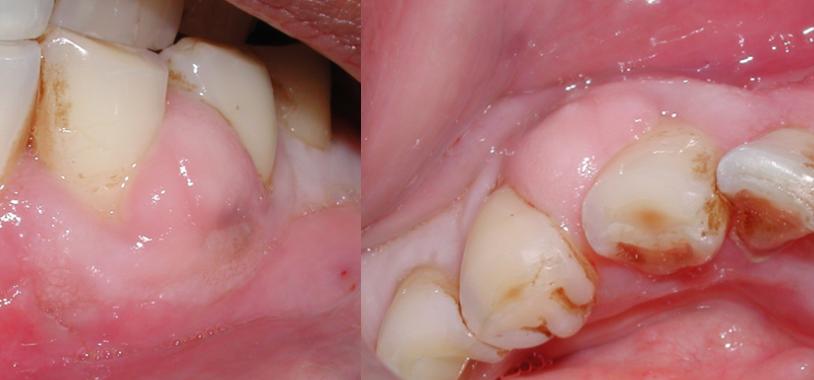

L'abces parodontal touche environ 25% des cas. L'infection part de l'exterieur de la dent, dans une poche parodontale profonde entre la dent et la gencive, formee par une parodontite (maladie des gencives) non traitee. La dent elle-meme est souvent vivante (pulpe saine), mais l'os qui la soutient est en train d'etre detruit. L'abces forme une "boule" rouge et tres douloureuse sur la gencive, souvent avec du pus qui sourd a la pression.

Le gonflement apparait 24 a 72 heures apres le debut de la douleur. D'abord localise a la gencive, il s'etend rapidement a la joue, au menton, parfois a l'oeil (abces des incisives superieures) ou au cou (molaires inferieures). Un visage deforme, asymetrique, chaud et douloureux au toucher est caracteristique d'une cellulite faciale, complication frequente de l'abces.